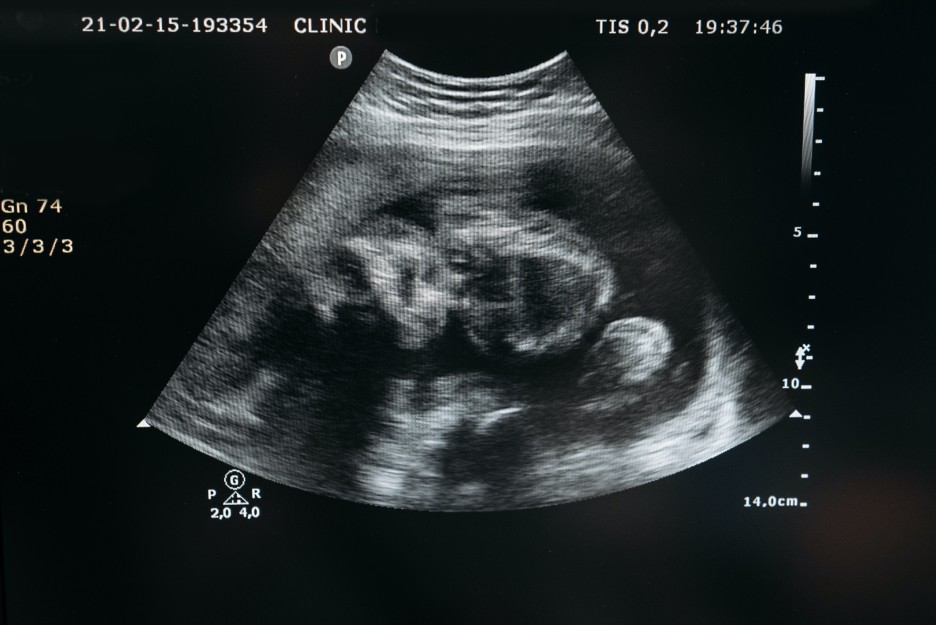

우리 아기를 산부인과에서 초음파 검사로 처음 만난 날..

쌍둥이는 태동을 하기 힘들까요?

태아가 태동할 때 양수에 의해 공간이 만들어져 움직일 수 있게 돼요.

쌍둥이의 경우 양수의 양이 혼자인 태아보다 많이 있기 때문에 공간이

좁을까 봐 걱정하지 않아도 된답니다.